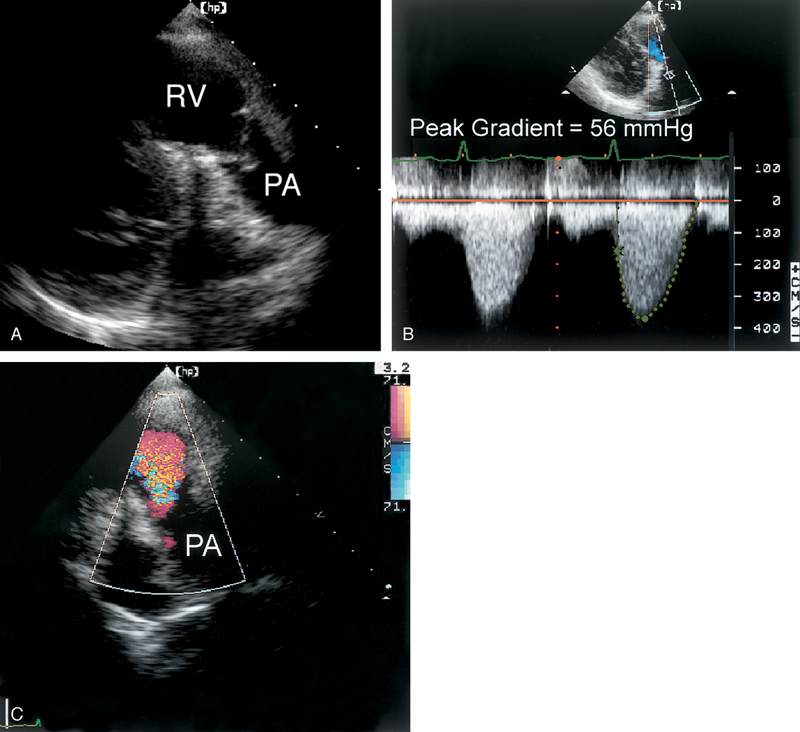

فحوصات تشخيصية لبعض امراض القلب والشرايين التاجية